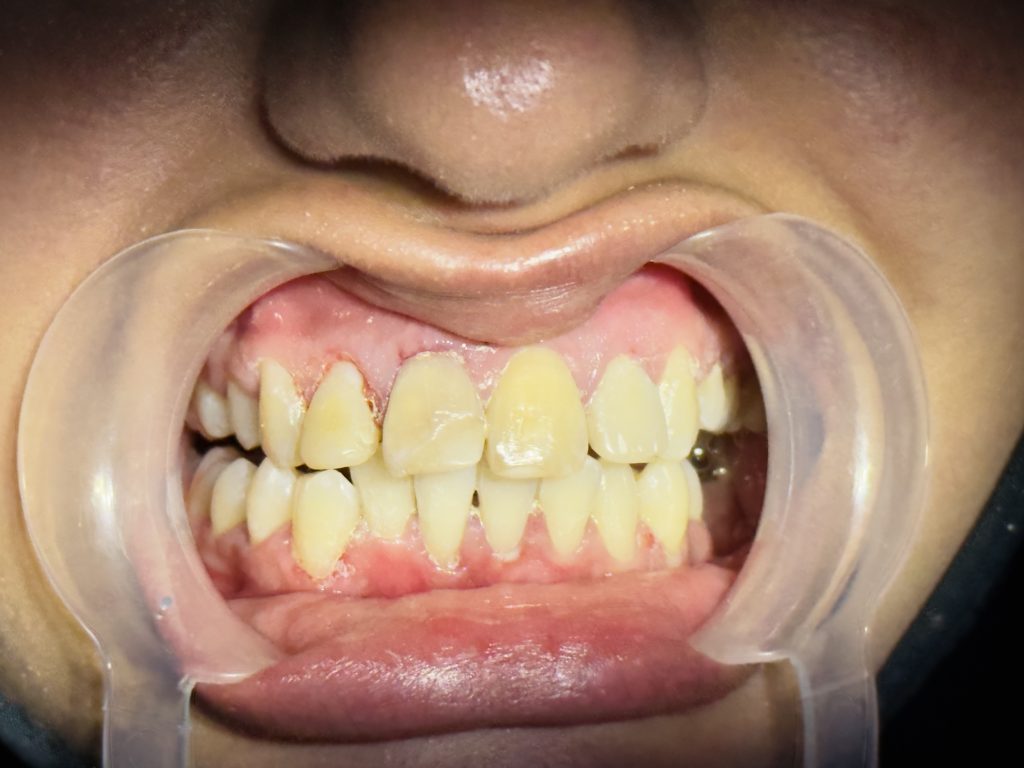

Result

- Smile completely transformed with natural esthetics and lifelike translucency.

- Gingival harmony and midline corrected digitally without orthodontics.

- Function restored with proper incisal guidance.

- Patient satisfaction: ⭐⭐⭐⭐⭐